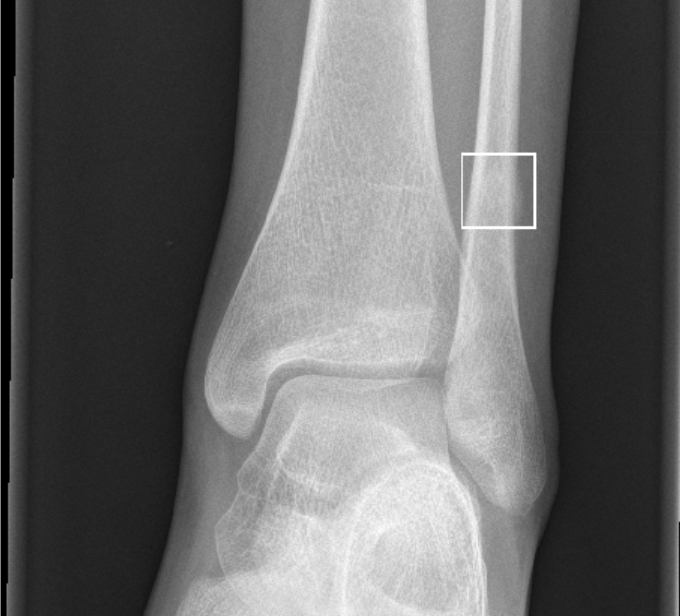

BoneView by Gleamer

Your AI assistant for bone trauma X-Rays. Highlight fractures on digital x-rays of extremities.